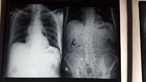

Ascaris lumbricoides and its almost deadly complication

Gabriel Alejandro Molina and others

Journal of Surgical Case Reports, Volume 2018, Issue 10, October 2018, rjy262, https://doi.org/10.1093/jscr/rjy262